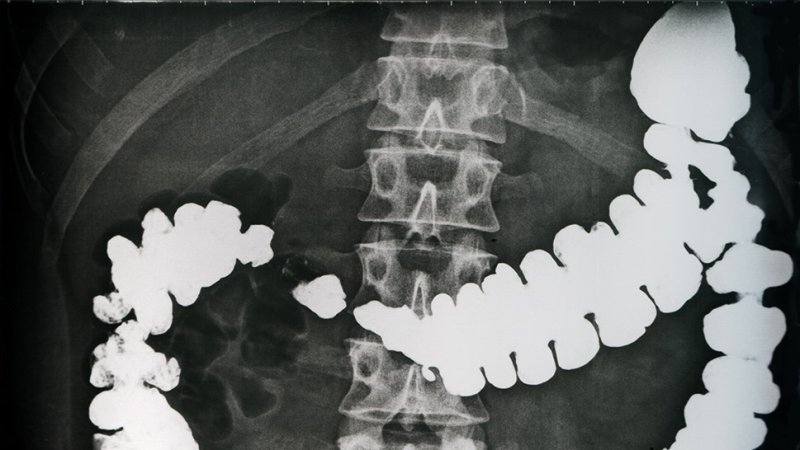

Prior to examination by computer tomography, the doctor administers a contrast medium solution to the patient.

Isotopes with a short half-life (primarily iodine 131I and technetium 99mTc) are used in medicine. They are used for contrast imaging, for identification of an organ’s functionality, or as a marker. They disintegrate in the patient’s body very quickly.